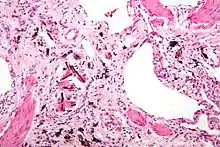

Asbestosis is the scarring of lung tissue (beginning around terminal bronchioles and alveolar ducts and extending into the alveolar walls) resulting from the inhalation of asbestos fibers. There are two types of fibers: amphibole (thin and straight) and serpentine (curly). All forms of asbestos fibers are responsible for human disease as they are able to penetrate deeply into the lungs. When such fibers reach the alveoli (air sacs) in the lung, where oxygen is transferred into the blood, the foreign bodies (asbestos fibers) cause the activation of the lungs' local immune system and provoke an inflammatory reaction dominated by lung macrophages that respond to chemotactic factors activated by the fibers.[20] This inflammatory reaction can be described as chronic rather than acute, with a slow ongoing progression of the immune system attempting to eliminate the foreign fibers. Macrophages phagocytose (ingest) the fibers and stimulate fibroblasts to deposit connective tissue.

Due to the asbestos fibers' natural resistance to digestion, some macrophages are killed and others release inflammatory chemical signals, attracting further lung macrophages and fibrolastic cells that synthesize fibrous scar tissue, which eventually becomes diffuse and can progress in heavily exposed individuals. This tissue can be seen microscopically soon after exposure in animal models. Some asbestos fibers become layered by an iron-containing proteinaceous material (ferruginous body) in cases of heavy exposure where about 10% of the fibers become coated. Most inhaled asbestos fibers remain uncoated. About 20% of the inhaled fibers are transported by cytoskeletal components of the alveolar epithelium to the interstitial compartment of the lung where they interact with macrophages and mesenchymal cells. The cytokines, transforming growth factor beta and tumor necrosis factor alpha, appear to play major roles in the development of scarring inasmuch as the process can be blocked in animal models by preventing the expression of the growth factors.[21][22] The result is fibrosis in the interstitial space, thus asbestosis.

Extensive fibrosis of pleura and lung parenchyma